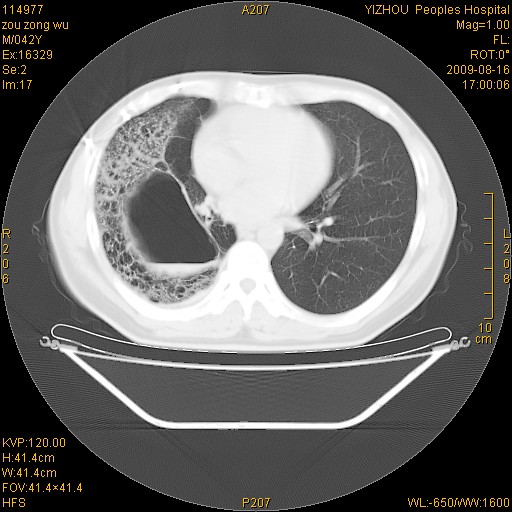

以下是引用zjzjr在2009-8-17 10:42:00的发言:[br]右侧间质性肺炎伴纤维化,右肺下叶肺囊肿伴感染(不除外外伤后引起),右肺野及胸壁软组织\\肝内见多发斑点状,中枪了吧.右侧胸膜肥厚\\粘连.